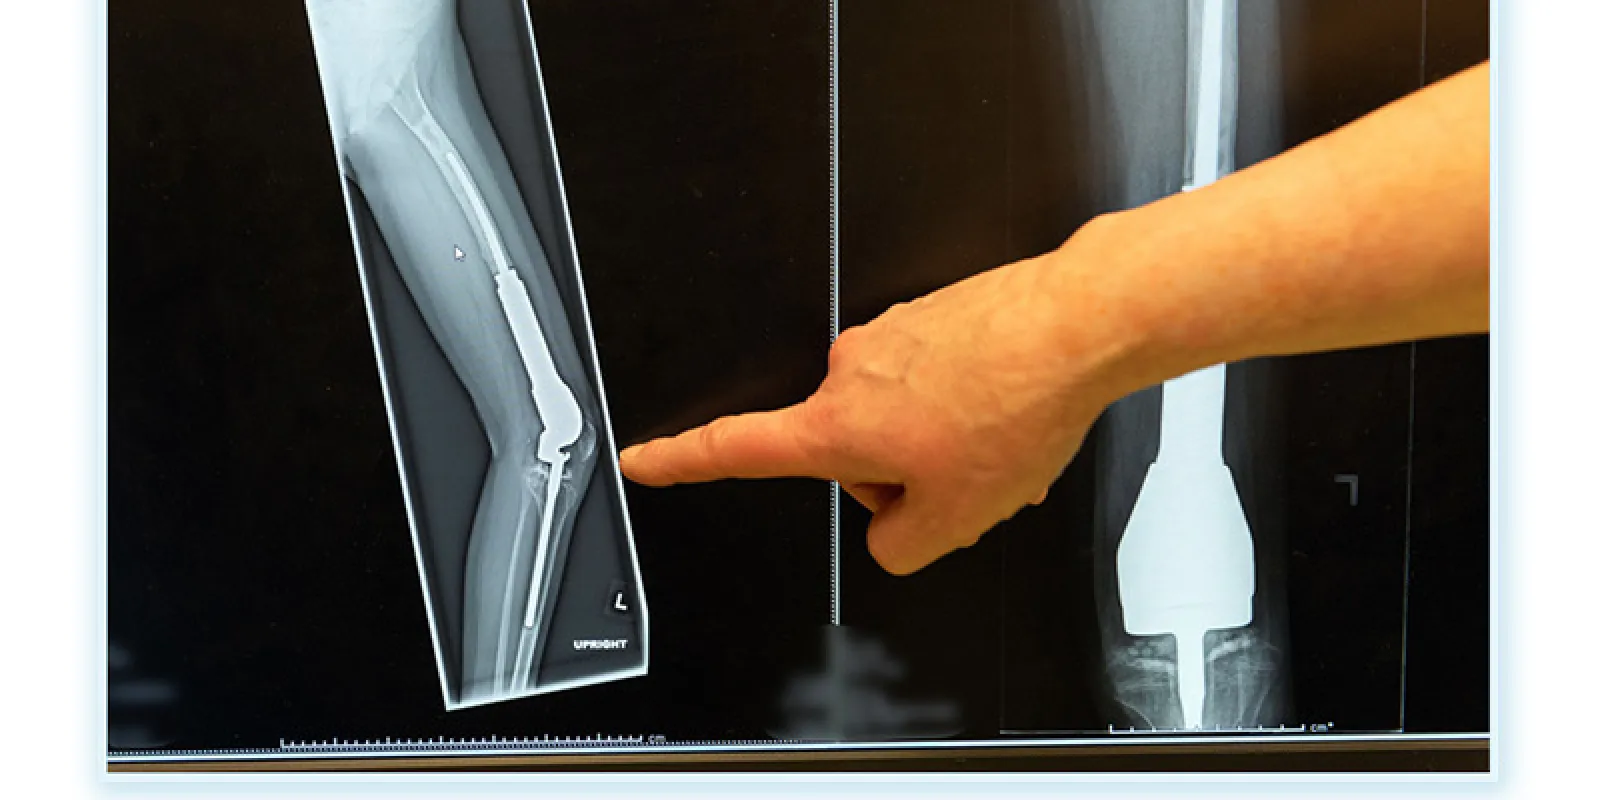

Limb-salvage surgery helps preserve the limb by removing the part of the bone involved with the tumor and some of the tissues that surround it. The bone is replaced with an implant, which can be either a bone graft or a metal prosthesis.

There are three main categories of implants used as part of limb-salvage surgery:

Limb-salvage surgery preserves an arm or leg by replacing cancerous bone with an expandable prosthesis.